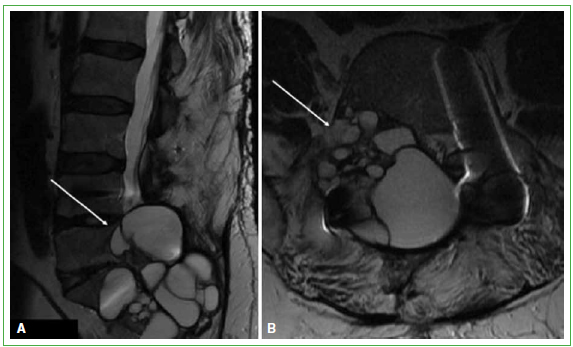

El paciente evoluciona de manera favorable. El control a las tres semanas indica M5 en L3-L5 y M4 en S1. Los antinflamatorios no esteroides disminuyen significativamente el dolor. En los controles en policlínico, continúa con disminución de fuerza en L5-S1 a derecha asociada a hipoestesia de las mismas metámeras. En 2014, comienza con un cuadro sintomático compatible con síndrome de cauda equina, con pérdida del control de esfínter urinario, por lo que se repite la resonancia magnética de columna lumbar que revela recidiva de lesiones de gran tamaño, a nivel lumbar intrarraquídeo. Se mantiene una conducta expectante y se reinicia albendazol 400 mg, cada 12 h, en ciclos de 2 meses, seguidos de 2 meses de descanso y control de pruebas hepáticas; la sintomatología cede (Figura 7). En la actualidad, no tiene compromiso de cauda equina, pero sufre una radiculopatía a nivel de L5 y S1 a derecha, como secuela, con adecuado control de esfínteres. Se mantiene la administración de albendazol en ciclos continuos de 2 meses, seguido de 2 meses de descanso.

Figura 7.

Resonancia magnética de columna lumbar. A y B. Cortes sagital y transversal. Se observan múltiples lesiones quísticas en relación con L4-L5 y S1, con compromiso intrarraquídeo. (Mayo de 2014).